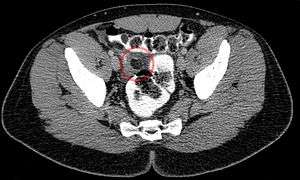

Epiploic appendagitis (EA) is an uncommon, benign, non-surgical, self-limiting inflammatory process of the epiploic appendices. Other, older terms for the process include appendicitis epiploica and appendagitis, but these terms are used less now in order to avoid confusion with acute appendicitis.

Epiploic appendices are small, fat-filled sacs or finger-like projections along the surface of the upper and lower colon and rectum. They may become acutely inflamed as a result of torsion (twisting) or venous thrombosis. The inflammation causes pain, often described as sharp or stabbing, located on the left, right, or central regions of the abdomen. There is sometimes nausea and vomiting. The symptoms may mimic those of acute appendicitis, diverticulitis, or cholecystitis. The pain is characteristically intense during/after defecation or micturition (espec. in the segmoid type) due to the effect of traction on the pedicle of the lesion caused by straining and emptying of the bowel and bladder. Initial lab studies are usually normal. EA is usually diagnosed incidentally on CT scan which is performed to exclude more serious conditions.